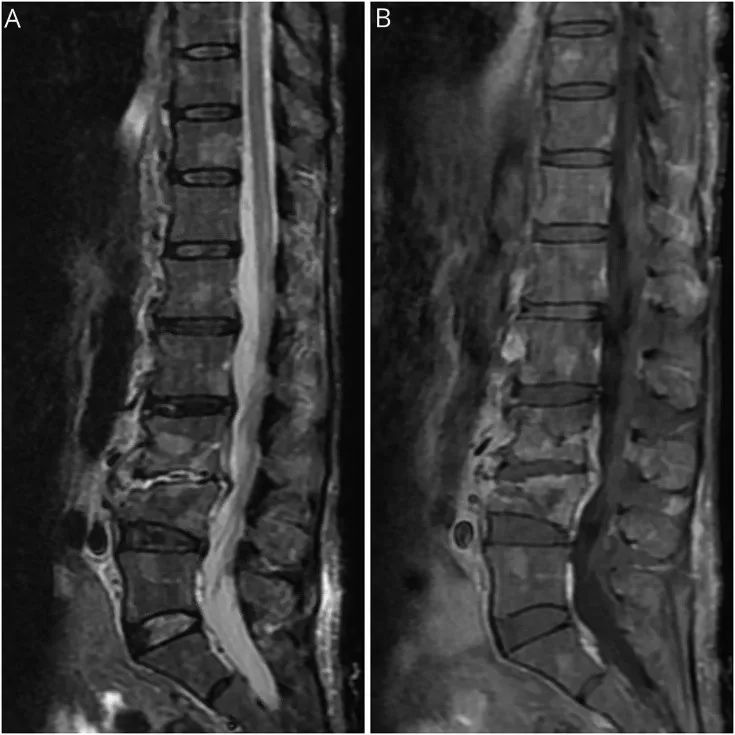

脊柱MRI(图)显示退行性变,受累椎体有MM,L3-L4压缩性骨折,但未显示出脊髓信号改变或受压,也未见马尾神经增强。值得注意的是,包括脊椎管和椎间孔狭窄在内的脊椎退行性变不能解释患者的神经功能障碍或EMG / NCS显示的去神经病变的程度。因此,神经影像学排除了弥漫性神经根受累的机械性病因。

图 脊柱MRI。短T1反转回复序列(STIR)矢状位(A)和T1增强矢状位(B)显示整个脊柱多个增强性、STIR高信号病灶,L3和L4椎体的病理性压缩性骨折,符合脊柱多发性骨髓瘤。此外,还可见弥漫性退行性改变,表现为多个水平的椎管和椎间孔狭窄。无脊髓信号异常或受压的表现。